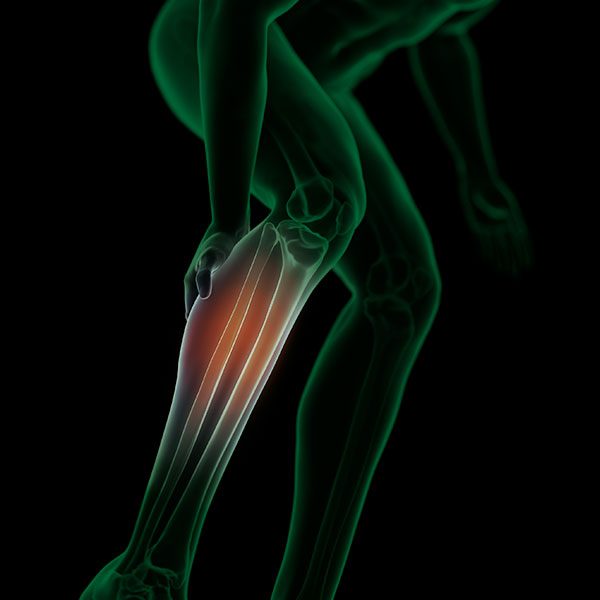

From www.palabraderunner.com

Periostitis tibial causas, tratamiento y ejercicios para aliviar el dolor Symptoms Of Periostitis Periostitis, or shin splints, is inflammation of the membrane that envelops the shinbone, often affecting runners. Learn about the causes, symptoms, diagnosis and treatment of tibial stress syndrome, a common overuse injury of the shin area. Periostitis is an inflammation of the periosteum, the connective tissue around the bone, often caused by overuse or injury. Learn about the types, diagnosis. Symptoms Of Periostitis.